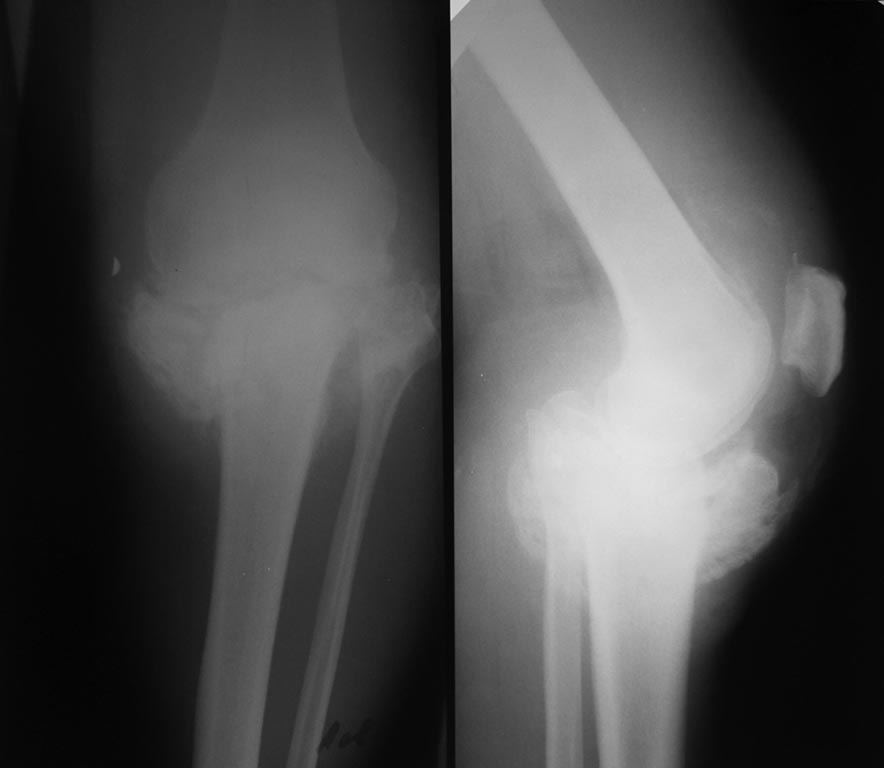

Рентгенограммы (1) январь 2015 год, (2) 25.05.2015 г.

Порочное положение конечности, объем движений: разгибание в к/суставе до

165 - 170 гр, сгибание до 105-110, выраженная хромота, болезненность при

нагрузках и в ночное время, но работать может. Онкоанамнез не отягощен,

Диагноз: Посттравматическая деформация проксимального отдела

большеберцовой кости как исход ее многооскольчатого (С3) перелома. По

срокам после травмы (более 6 мес): Ложный сустав (неоартроз)